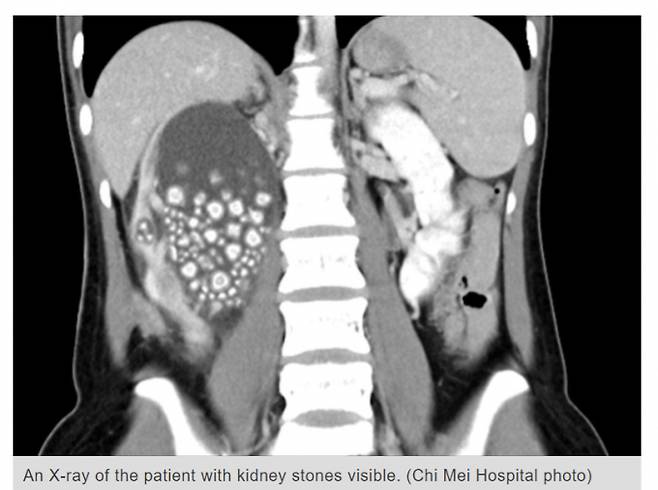

지난 10일(이하 현지시각) 타이완 뉴스 등에 따르면 20대 여성 A씨는 최근 열 증상과 함께 허리에 심각한 통증이 있어 병원을 찾았다. 엑스레이 촬영 결과 그의 신장은 수백개의 크고 작은 결석으로 인해 부풀어 오른 상태였다.

A씨의 신장에서 제거한 결석은 300개 이상으로 직경 0.5~2㎝였다. 현재 A씨는 외래 진료를 받으며 건강을 회복 중인 것으로 전해졌다.